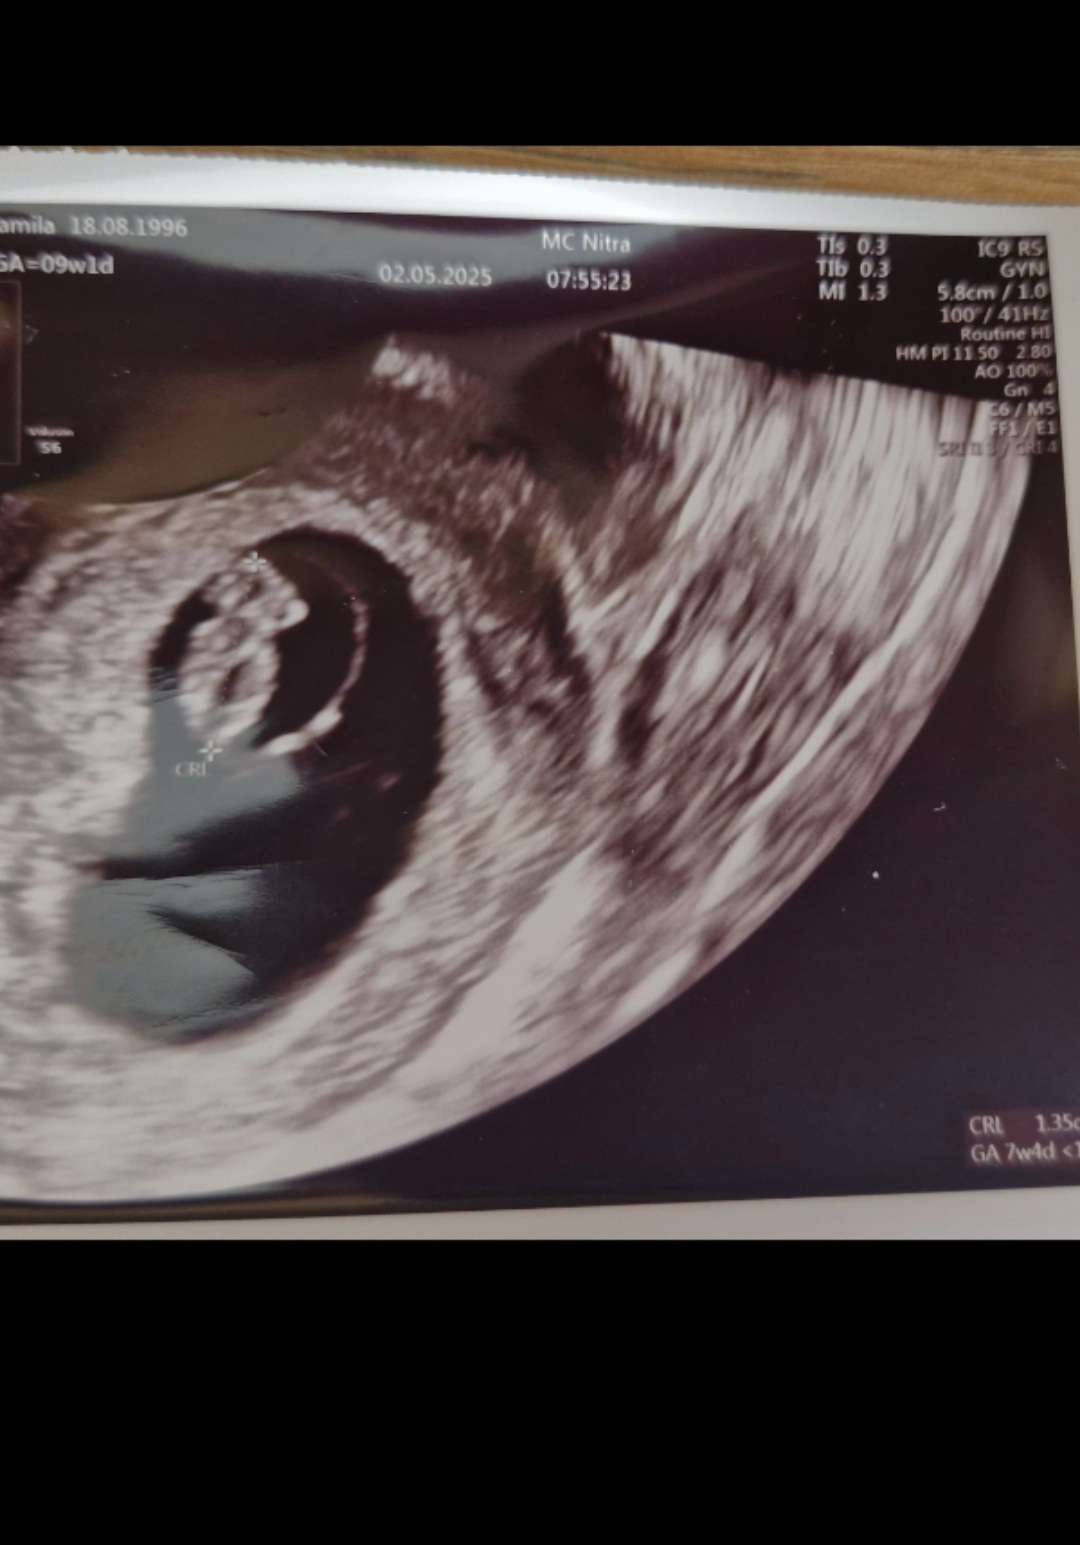

Tak som rada 😊 píše sa tam 9tt+1

Takže gynekologicky si v 9 týždni+ 1 deň

Ale berie sa to ako 10 týždeň (v tomto som mala guláš pekne dlho kým som pochopila ako to berú)

Myslím, že číslo v ľavom hornom rohu je podľa dátumu poslednej menštruácie - to si 9+1. A v pravom dolnom rohu je hodnota podľa veľkosti plodu - 7+4 (takže si asi mala ovuláciu trochu neskôr).